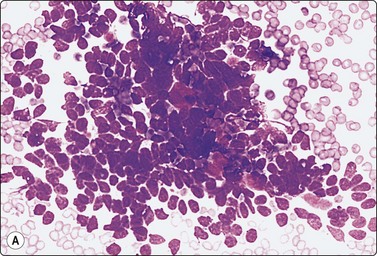

image image image

Fig. 14.9 Cystic eccrine hidradenoma

Loose clusters of basaloid cells with small, dark, uniform nuclei in a background of proteinaceous fluid (A, MGG; B, Pap, IP); (C) Corresponding tissue section (H&E, LP).

The cytology of nodular hidradenoma30-32 and of clear cell hidradenoma33,34 has been described in single cases. A benign skin adnexal tumor from our files, histologically reported as cystic eccrine hidradenoma, is shown in Figure 14.9. The FNB sample was of mucoid fluid which contained clusters of variably cohesive uniform epithelial cells with a moderate amount of cytoplasm and small dark ovoid nuclei. A dual population was not discernible. The cytology was reported as a benign skin adnexal tumor without further specification.